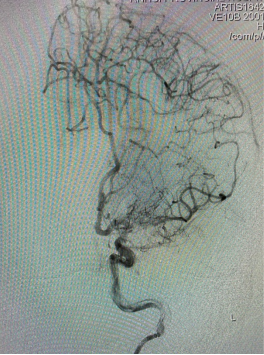

DSA显示左侧大脑中动脉M1段闭塞,大脑前动脉通过软膜支代偿,后循环无代偿。

全麻后全身肝素华,左侧颈内动脉置入6F ENVOY导引导管,Transend微导丝小心进入斑块并通过闭塞处,Enchlon10微导管在微导丝的导引下通过狭窄处至远端,微导管造影显示位于血管真腔,交换Transend300微导丝,撤出微导管,沿微导丝把SacSpeed颅内球囊(2.0-12mm)送至血管闭塞处,充盈扩张球囊预扩后造影显示M1段再通,残余狭窄约30%,观察20分钟再次造影显示残余狭窄增加,再次予球囊扩张,沿微导丝置入Prowler Select Plus支架导管后顺利释放Enterprise2支架(4.0-23mm支架)一枚,造影显示支架贴壁良好,左侧大脑中动脉M1段通畅良好。

释放支架,造影显示贴壁良好。

术后即刻造影显示闭塞处血管再通良好